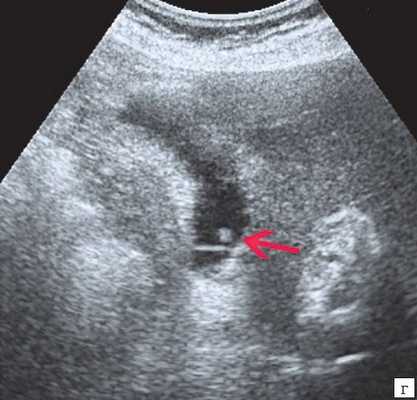

Ультрасонография является эффективным средством выявления полиповидной формы холестероза 6. Традиционной считается следующая сонографическая характеристика холестериновых полипов: неподвижные гиперэхогенные структуры, которые не дают акустической тени и прикрепляются к стенке желчного пузыря. Контуры таких образований, как правило, ровные, а размеры таких образований различны, чаще не превышают 10 мм (рис. 2).

г) Одиночный полип в желчном пузыре.

Однако, по некоторым данным, размеры холестериновых полипов могут быть более 20 мм. Кроме того, полипы больших размеров (в 7% от общего числа) могут иметь пониженную эхогенность и фестончатый контур.